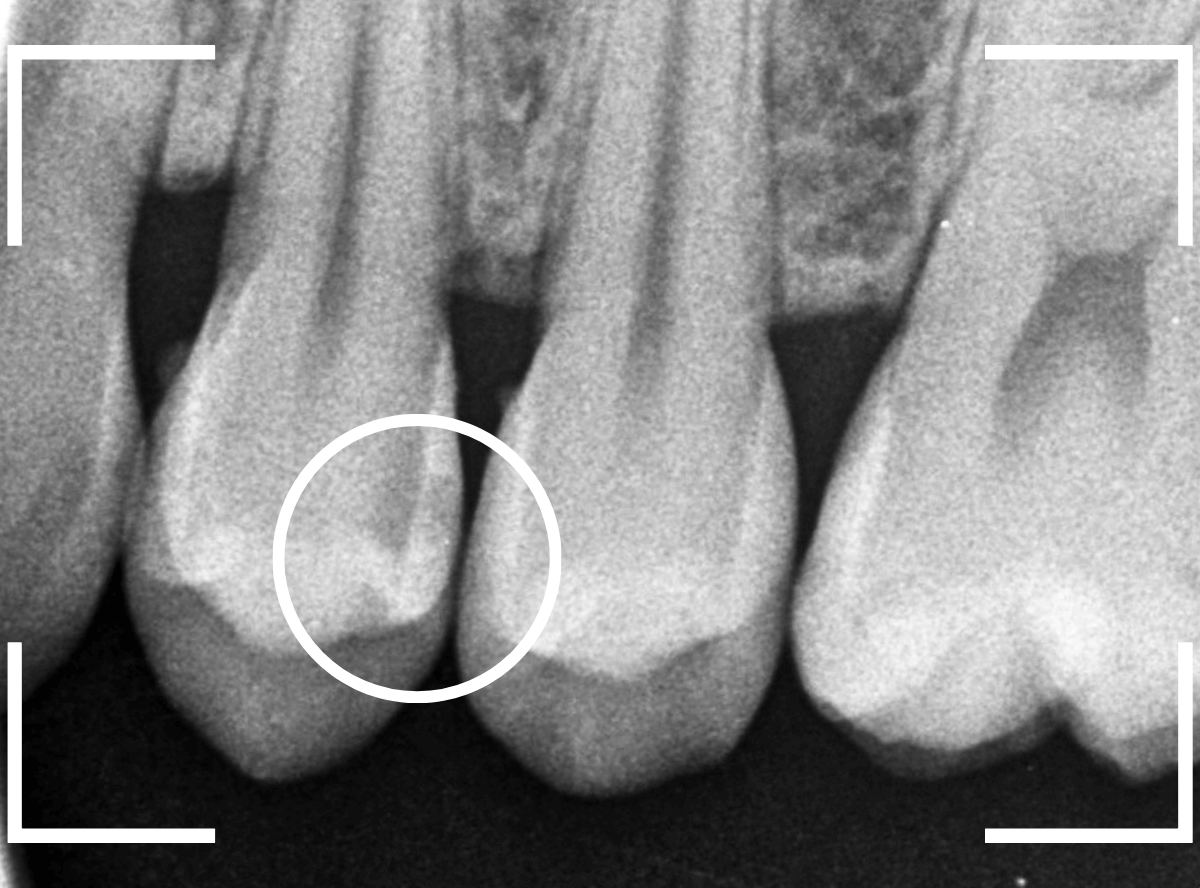

Case.22 痛みはないけど、歯のすきまから大きな虫歯

上の小臼歯の間が虫歯になっていた患者さんです。

症状はありませんし、見た目からも虫歯があるかはわかりませんでした。

レントゲン写真で確認します。

赤い線が虫歯、青い線が歯の神経です。

歯のすきまから両側に虫歯が大きく広がっているのが確認できます。